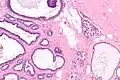

| Micrograph of collagenous spherulosis with the characteristic histomorphology - intratubular eosinophilic material with a spoke-like arrangement. H&E stain. | |

Collagenous spherulosis is characterized by a tubular/cribriform architecture with intratubular eosinophilic material that classically is arranged like the spokes of a wheel ("radial spikes"). There is usually no mitotic activity, and two cells populations (epithelial & myoepithelial) are present, like in benign breast glands.